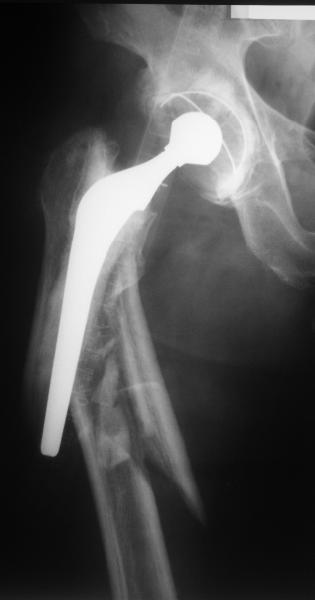

Мужчина 59 лет, переведен к нам через >6 нед после автотравмы, сбит машиной. 5 лет назад цементное проезирование DePuy Elite+

Как классифицировать этот перелом? Ножка мне кажется стабильной, т.е. Vancouver B1? Или B2?

Сейчас есть варус и укорочение, ручная тракция уже не устраняет смещение.

Думается про ретроградный гвоздь, который присоединяется к ножке протеза. Еще не доводилось такого делать на цеметной ножке.

Dear All. A male 59 y.o. referred to our unit >6 weeks after car accident. Initially managed on traction. Cemented THR 5 years ago (DePuy Elite +).

How would you estimate the fracture - the stem looks stable, i.e. Vancouver B1. Or B2?

Now the femur is deformed to varus and shortened, manual traction already not enough to restore length/axis.

I think about custom-made retrograde nail which connects to the stem.

Never performed it to a cemented stem. Some site opening may be necessary to remove at least pieces of broken cement mantle. Also application of an ex-fix for longitudinal traction looks useful.